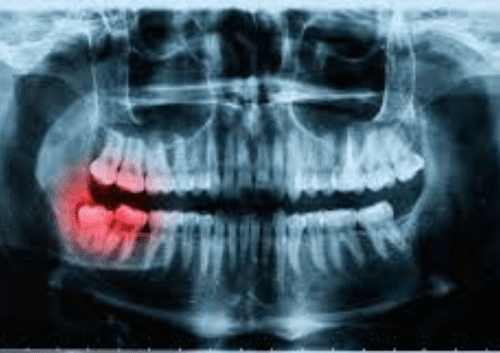

Because tooth decay has numerous stages, there are a variety of symptoms that you may see, feel, or even taste at times. The treatment you will require for your cavity will be determined by how serious the decay is and where it is located. Stage 1: The enamel is decaying. A cavity has not yet passed through the enamel, which is the outer coating of the tooth, during its early stages. During this period, symptoms are not very severe. In fact, you might not notice any of them at all. Sometimes, you may notice that your tooth has darkened, or you may feel a little sensitivity. Our Summerlin dentist will remove the area that has enamel decay and fill the empty space with a tooth-colored filling material in order to repair the decay. Fillings are a quick and inexpensive option that can last for many years. Stage 2: Dentin After the decay has passed through the enamel surface, it will reach the dentin layer. The dentin layer is fragile and is particularly susceptible to decay. This means that if the cavity reaches the dentin, it can spread quickly. During this stage, you will notice that your tooth sensitivity is more pronounced. You might feel uncomfortable when you eat sweets, clean your teeth, or are in chilly conditions. If the decay has impacted much of your tooth, our dentist in Summerlin may suggest that you get a crown instead of a filling. A crown is a hard cap that goes over your tooth and protects it from further harm. Because this treatment is more complex, it does take longer to finish. Additionally, it is more expensive than simply a basic filling. However, if crowns are manufactured and maintained correctly, they can last for many years, making your investment worthwhile. Stage 3: Pulp Chamber The decay will enter the pulp chamber once it has passed through the dentin layer. This is the section of the tooth that has blood arteries, nerves, and connective tissue. Your tooth will become infected after the cavity has reached the pulp. You will go through a lot of discomfort during this time. You may also start to feel uncomfortable due to heat, in addition to chilly weather. You may also experience persistent discomfort that necessitates the use of pain medication to alleviate it. We will take an x-ray of your tooth to make sure that the cavity has reached the pulp chamber. Root canal therapy will be necessary to fix and protect your tooth. This surgery consists of taking out the nerve tissue, cleaning the canals, and closing them off in order to stop bacteria from coming back in. You will probably need to be fitted for a crown in addition to receiving therapy on the nerves of your tooth. This will help to prevent additional harm to the tooth that is already at risk. Stage 4: Abscess The roots of your teeth are the parts that you cannot see when you look inside your mouth. They are located in the jaw. Nerve channels that go down each root extend beyond the pulp chamber. If your cavity has reached the nerves in the root of your tooth, you may have a terrible pain and swelling in your face. If you have an abscess, you will see a little bump on your gums, which is called a fistula. A dental abscess is a major medical issue. You might not find any relief from over-the-counter pain drugs. The toothache could prevent you from sleeping at night or cause you to wake up often. The gum tissue surrounding the tooth that is impacted may swell, and this swelling could migrate to your face. You might possibly develop a fever. If a cavity has caused a serious infection, it may not be possible to salvage the tooth with a root canal. It may be essential to do an extraction. We will be able to determine the state of your tooth and if it can be saved by using a dental x-ray. If it turns out that we need to take it out, a dental implant or a bridge could be a good option for you to replace it. Preventing Cavities Maintaining excellent dental hygiene is the most effective approach to avoid cavities. Make sure to have frequent cleanings and check-ups with your dentist in Las Vegas so that any problems can be addressed as soon as they arise. If you haven't gone to the dentist in a while or think you might have a cavity, you should make an appointment with Dr. Cohan at Summerlin Dental Solutions. Make an appointment by calling or book online today. GET TO KNOW YOUR BEST DENTIST IN SUMMERLIN